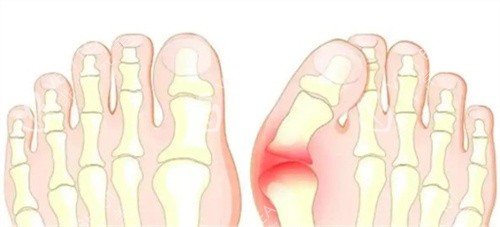

拇外翻,也就是我们常说的“大脚骨”,不仅影响脚部美观,还可能引发疼痛,影响日常行走。很多饱受拇外翻困扰的人会选择通过手术来矫正,然而,令人头疼的是,部分人在矫正后却出现了复发的情况。今天,就带大家揭秘拇外翻矫正后可能复发的3大原因。

除了手术和护理方面的原因,患者自身的一些因素也可能导致拇外翻复发。比如,遗传因素在拇外翻的发病中起着重要作用,如果家族中有拇外翻患者,那么患者本身的足部骨骼结构可能存在一定的缺陷,即使通过手术矫正,复发的风险也相对较高。